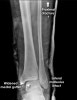

X-ray : Maisonneuve fracture